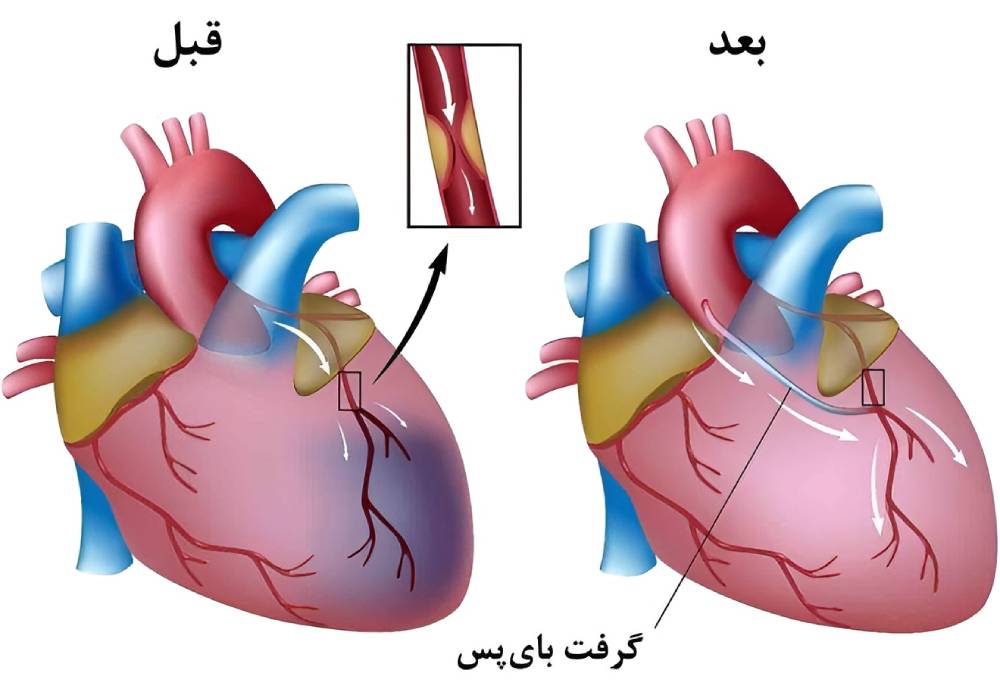

جراحی بایپس

جراحی بایپس شریان کرونری مسیر جدیدی را برای جریان یافتن خون دور شریان قلب مسدود یا با گرفتگی جزئی ایجاد میکند. متخصص قلب رگ خونی سالمی را از قفسۀ سینه یا پا برمیدارد. سپس رگ پیوندی را به زیر شریان مسدود قلب متصل میکند. مسیر جدید جریان خون را در عضلۀ قلب بهبود میدهد.

متخصص قلب جراحی بایپس شریان قلب را در شرایط زیر توصیه میکند:

- اگر انسداد در شریان اصلی سمت چپ قلب باشد: این شریان خون فراوانی را به عضلۀ قلب میرساند.

- چنانچه تنگی شریان اصلی قلب شدید باشد.

- اگر بیمار به دلیل گرفتگی چند شریان قلب دچار درد شدید قفسۀ سینه باشد: تنگی شریان جریان خون را در قلب، حتی هنگام ورزش سبک یا استراحت کاهش میدهد.

- چنانچه بیش از یک شریان قلب گرفته باشد و حفرۀ (بطن یا دهلیز) سمت چپ پایین قلب به خوبی کار نکند.

- اگر گرفتگی شریان را نتوان با آنژیوپلاستی درمان کرد: آنژیوپلاستی درمانی کمتهاجمی است که در آن از بالن قرارگرفته بر سر لولۀ باریکی به نام کاتتر برای گشاد کردن شریان استفاده میشود. متخصص قلب معمولاً از کویل کوچکی به نام استنت برای باز نگه داشتن شریان استفاده میکند.

- چنانچه آنژیوپلاستی با یا بدون استنتگذاری مؤثر نبوده باشد: برای مثال شریان پس از استنتگذاری دوباره تنگ شده باشد.

مراحل انجام عمل بایپس قلب

جراحی بایپس شریان کرونری عمل مهمی است که در بیمارستان انجام میشود. پزشکان آموزشدیده در زمینۀ جراحی قلب، موسوم به جراحان قلب و عروق این عمل را انجام میدهند. متخصص قلب یا کاردیولوژیست و گروهی از پزشکان مراقب بیمار هستند.

قبل از منتقل شدن به اتاق عمل سرمی به ورید بازو یا دستتان متصل میشود تا داروی آرامبخش دریافت کنید.

اقدامات زیر در اتاق عمل انجام میشود:

- بیهوشی: ترکیبی از داروها را از طریق سرم و ماسک صورت دریافت میکنید. این داروها شما را در حالتی خوابمانند و بدون درد قرار میدهند. به این حالت بیهوشی عمومی میگویند.

- دستگاه تنفس مصنوعی: متخصص لولۀ تنفسی را وارد دهانتان میکند. این لوله به دستگاه تنفسی به نام ونتیلاتور متصل میشود. این دستگاه تنفس را در طول عمل و بلافاصله پس از عمل برایتان انجام میدهد.

- ماشین قلب و ریه: ماشین قلبی_ریوی خون و اکسیژن را در طول جراحی در سراسر بدن به جریان میاندازد. به این عمل بایپس کرونری با پمپ میگویند.

جراحی بایپس شریان قلب معمولاً سه تا شش ساعت طول میکشد. مدت زمان جراحی به تعداد شریانهای مسدودشده بستگی دارد.

جراح معمولاً برش بزرگی را در مرکز قفسۀ سینه در امتداد جناغ سینه ایجاد میکند. سپس قفسۀ سینه را باز میکند تا قلب مشخص شود. قلب پس از باز کردن قفسۀ سینه موقتاً با دارو متوقف میشود. ماشین قلبی_ریوی روشن میشود.

جراح بخشی از یک رگ سالم را برمیدارد، رگ پیوندی غالباً از داخل دیوارۀ قفسۀ سینه یا از پایین پا گرفته میشود. به این تکه از بافت سالم گرفت یا بافت پیوندی میگویند. جراح دو سر گرفت را به زیر شریان قلب مسدود متصل میکند. به این ترتیب مسیر جدیدی برای جریان یافتن خون دور انسداد ایجاد میشود. در یک عمل بایپس ممکن است از بیش از یک گرفت استفاده میشود.